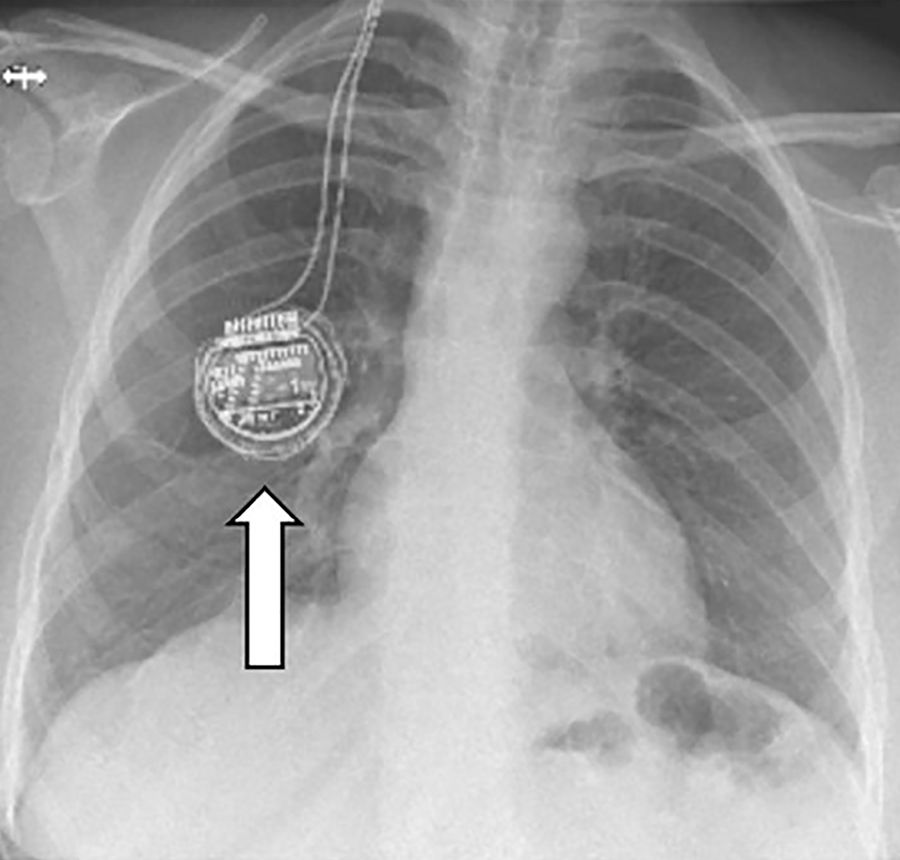

Die Vagusnervstimulation ist ein neuromodulatives Verfahren, das zur Behandlung von therapieresistenter Epilepsie eingesetzt wird. Dabei wird ein kleiner Impulsgenerator unter der Haut im Brustbereich implantiert, der elektrische Signale über eine Elektrode an den linken Vagusnerv sendet.Durch die Stimulation kann die Häufigkeit von epileptischen Anfällen reduziert werden, wenn andere Behandlungsansätze nicht ausreichend wirksam sind.